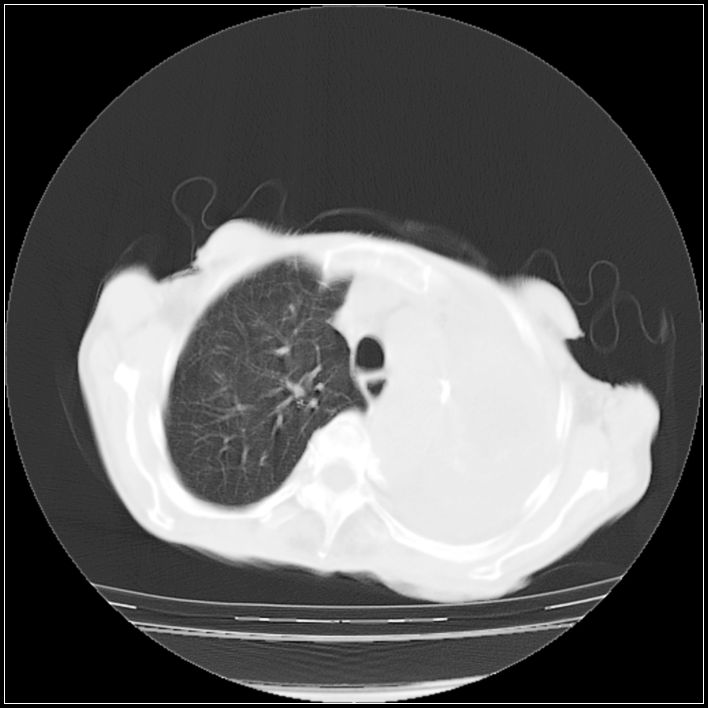

以下是引用ydx_74在2008-5-31 16:08:00的发言:[br]中心性肺癌并左侧肺不张、胸水。

以下是引用影象小辈在2008-5-31 16:25:00的发言:[br]左侧胸腔团状不规则致密影,界欠规整,密度不均匀,其内可见更低密度影及高密度影,并可见包裹性胸腔积液 考虑为1.畸胎瘤 2.肺癌